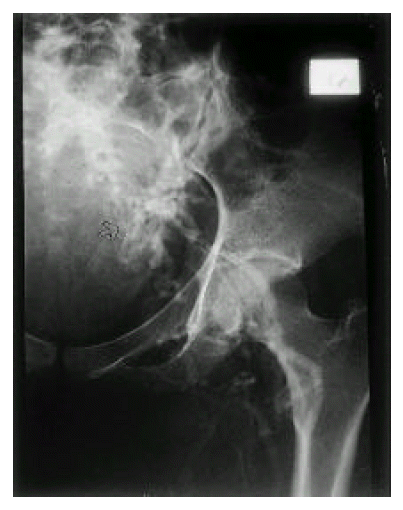

A 26-year-old woman was admitted for dyspnea, coughing and generalized edema for the last 5 months. She had a symptoms complex of recurrent oral aphtous ulcer, genital ulcer, erythema nodosum like skin lesions, uveitis and positive Pathergy test, and was diagnosed to have BD according to the diagnostic criteria proposed by the International Study Group for Behçet’s disease5). She gave no history of smoking, consumption of alcohol or any drugs. Two years ago, bypass surgery was performed due to deep vein thrombosis of left lower extremity (Fig. 1, 2). At that time, she did not follow-up and was not prescribed for any medication. On physical examination, the patient was uncomfortable and slightly pale. She became dyspneic on supine for the examination. No rash or lymphadenopathy was found. There was marked edema over the face, neck, both shoulders, anterior chest and lower extremities. Also, collateral vessels formation in the anterior chest wall and abdomen were noticed. Diminished breath sounds were present over both lung fields. The abdomen was distended and non-tender, but a fluid wave and shifting dullness were present. The liver was palpable 5 cm below the costal margin, but the spleen was not felt and no masses were palpable.

Fig. 1.

Venography of left lower extremity. Left iliac vein is obliterated and multiple collateral veins (arrow) are shown.